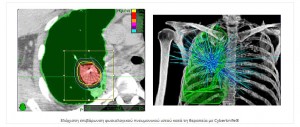

Η ακτινοχειρουργική με CyberKnife αντιπροσωπεύει μία πανίσχυρη και μεγάλης ακρίβειας τεχνική για ασθενείς με αρχική, υποτροπή ή μεταστατική εντόπιση όγκου στον πνεύμονα. Η θεραπεία είναι ασφαλής να δοθεί σε ασθενείς που δεν μπορούν λόγω άλλων παθολογικών καταστάσεων να χειρουργηθούν και προσφέρει μία πολύ καλή θεραπευτική επιλογή σε ασθενείς με υποτροπιάζουσα ή εμμένουσα νόσο που πριν είχαν ελάχιστες αν όχι καμία, δραστική θεραπεία ικανή να τους βοηθήσει.

Το CyberKnife είναι ένα σύστημα ακτινοθεραπείας που αποτελείται από ένα γραμμικό επιταχυντή τοποθετημένο επάνω σε έναν ρομποτικό βραχίονα.

Το CyberKnife είναι ένα σύστημα ακτινοθεραπείας που αποτελείται από ένα γραμμικό επιταχυντή τοποθετημένο επάνω σε έναν ρομποτικό βραχίονα.